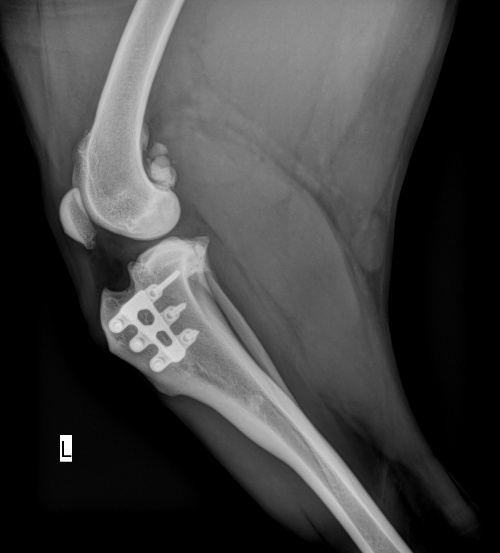

Over time, the bone integrates with the implant, gradually restoring complete stability. The accompanying image depicts the same TTA RAPID® cage 16 months post-surgery, showcasing how the bone has successfully grown through the implant, a testament to the innovative design of the TTA RAPID® cage.

X-Ray image 16 months after the TTA RAPID® Surgery →